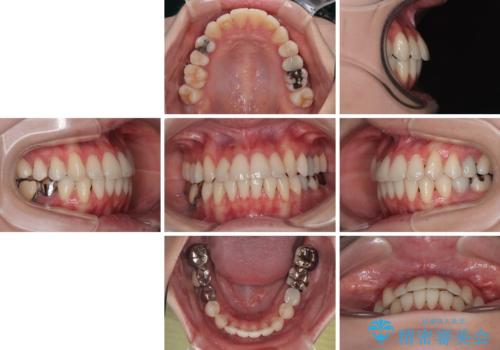

【モニター】前歯のデコボコをインビザラインで綺麗に

- 上下前歯のデコボコとクロスバイトを気にして来院された患者様です。

治療済みの処置歯が多いため、インビザラインを用いて矯正治療を行うこととしました。

下顎臼歯部にブリッジが装着されており、移動不可のため、IPR(歯と歯の間を削る)と歯列全体を拡大させることで、歯並びを整えていくこととしました。

インビザライン特有の奥歯の噛みにくさが治療後半に発現しましたが、無事に終了させることができました。